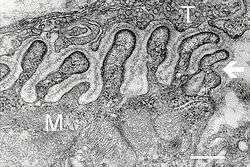

![]() Electron micrograph showing a cross section through the neuromuscular junction. T is the axon terminal, M is the muscle fiber. The arrow shows junctional folds with basal lamina. Active zones are visible on the tips between the folds. Scale is 0.3 µm. Source: NIMH | |